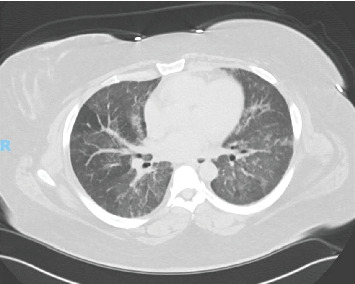

Background: Diffuse alveolar hemorrhage (DAH) is a potentially life-threatening condition which can present with hemoptysis, diffuse alveolar infiltrates, anemia, and hypoxic respiratory failure. Antisynthetase syndrome (AS) is a rare autoimmune disorder most often characterized by nonerosive arthritis, proximal muscle weakness with elevated muscle enzymes, Raynaud's phenomenon, hyperkeratosis of the digits (mechanic's hands), and interstitial lung disease. According to large population studies, AS has an annual incidence of 0.56 per 100,000 persons and prevalence of 9 per 100,000. The most common autoantibody is anti-aminoacyl-transfer RNA synthetase for histidine (anti-Jo-1) with a reported prevalence of 20%-30%, whereas anti-Pl-7 (for threonine) accounts for less than 5% of all autoimmune myositis. Specific myositis autoantibodies determine clinical phenotype. PL-7 is characterized by interstitial lung disease, myositis, and arthritis. Autoimmune myositis, specifically AS, is a rare cause of DAH. Herein, we describe the first reported case of PL-7-associated AS with DAH. Case Presentation: A 41-year-old female presented with worsening shortness of breath and hemoptysis. Laboratory studies included a hemoglobin of 10.5 g/dL, mildly elevated liver enzymes, and a creatine phosphokinase (CPK) of nearly 4000 U/L. CT of the chest showed diffuse ground glass opacities bilaterally. Serial aliquots of the bronchoalveolar lavage (BAL) fluid revealed progressively hemorrhagic return and histopathologic analysis consistent with DAH. Other concurrent causes of DAH were ruled out. Conclusion: Although rare, AS should be considered a cause of DAH, particularly in patients presenting with symptoms of muscle weakness and arthritis or with evidence of mechanic's hands.

Abstract Image